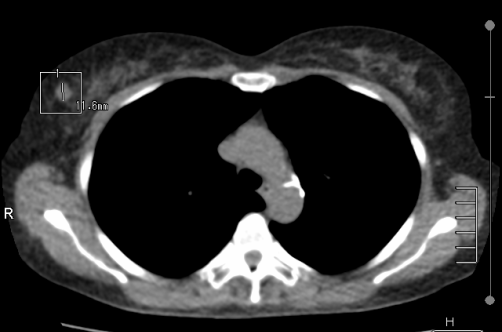

乳房病變以乳房攝影與超音波為基本篩檢工具,對於細微的變化CT是毫無置喙之處,但若看見明顯病灶仍有值得一提的時候。有位58歲退休副護理長在LDCT時發現右乳房有新增軟組織結節 (圖2),經乳房超音波檢查後高度懷疑是乳癌 (BI-RADS 4B),3星期後手術證實是侵犯性乳管癌第二期。

圖二.顯示右側乳房有新增軟組織結節11.6 mm